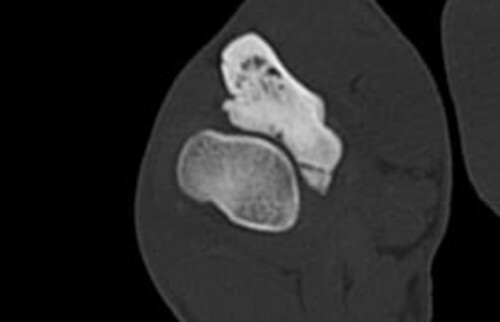

Nach der klinischen Diagnose werden die Hunde in unserer Klinik direkt im Computertomografen untersucht, sodass genau beurteilt werden kann, welche Gelenksanteile wie schwer betroffen sind, um eine individuelle Therapie festzulegen.

Schwarz-weiss Röntgenaufnahme